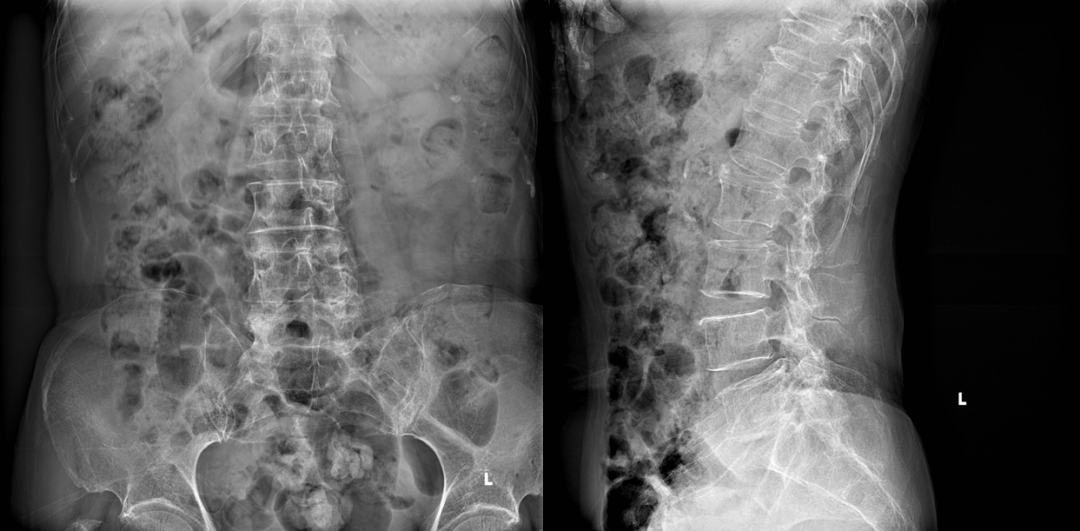

术前DR

接诊后,中山三院脊柱外科派驻中山三院粤东医院的专家刘仲宇主任指导团队为苏女士进行了系统评估。通过详细的病史询问、体格检查并结合影像学资料,刘主任敏锐发现其右下肢疼痛根源并非此前其他医院诊断的“腰椎间盘突出”、“肌肉劳损”或者“神经系统病变”,而很可能是由L5-S1右侧椎间孔狭窄导致的右侧L5神经根受压所引起。“椎间孔是神经根穿行的通道,当这个空间因骨质增生、韧带肥厚等原因变窄时,神经就会被卡住,引发剧烈疼痛。”刘主任解释道。